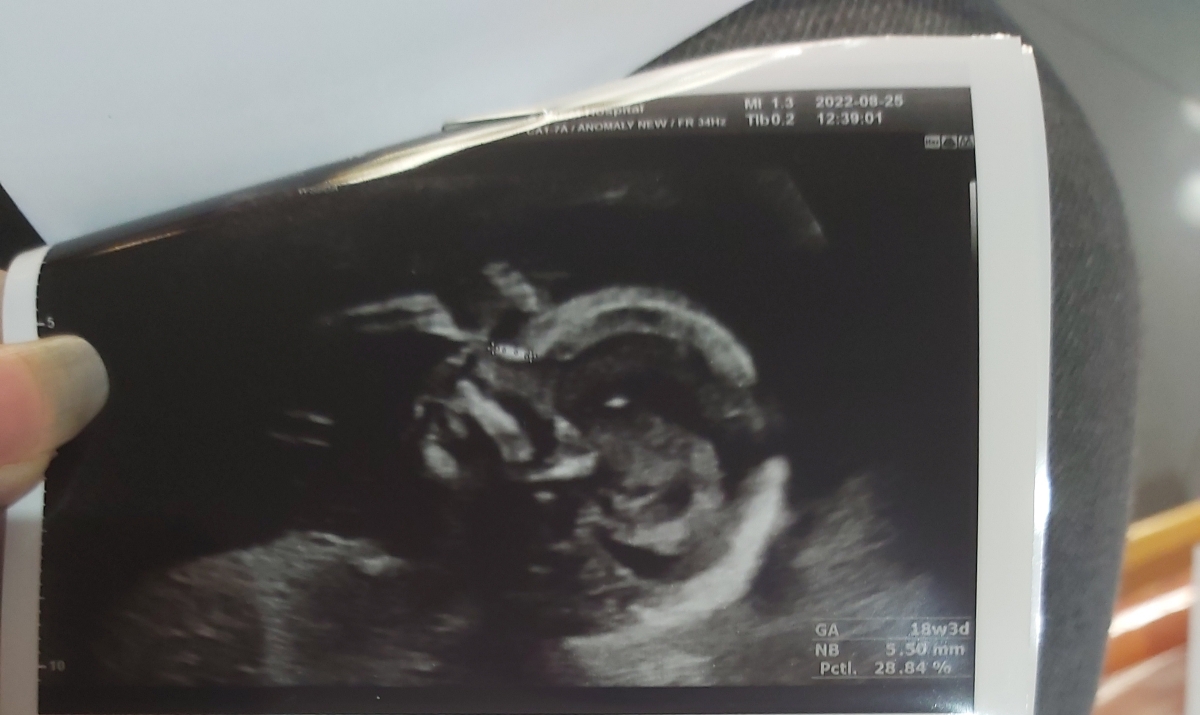

من سونو آنومالی و انجام دادم لطفا تفسیرش کنید ببینید همه چی خوبه؟؟

عزیزجانم تکرار ntd screen باز هم همان نتیجه را در پی داشته و بنابراین باید سونوگرافی آنومالی اسکن به شکلی که صحبت شده بود در فواصل منظم تکرار گردد اما در رابطه با سونوگرافی آنومالی اسکن فعلی انجام شده خوشبختانه همه چیز خوب بوده و شباهتی به نفع لوله عصبی مشاهده نشده است تنها دو نکته حائز اهمیت است که باید به آنها توجه داشته باشید نکته اول اینکه دو دور بند ناف دور گردن جنین پیچیده شده که اگرچه بند ناف اندامی نرم، شل و بلند است و غالباً در تحرکات جنین چرخش ها خود بهخود باز شده و هیچ مشکلی را برای جنین ایجاد نمیکنند اما بهتر است در بارداری با سونوگرافی داپلر شرایط همچنان تحت پایش باشد و از زمانی که حرکات را احساس می کنید با دقت روی آنها تمرکز داشته باشید نکته دوم این است که شواهدی به نفع چسبندگی جفت دیده شده که باید با تکرار سونوگرافی کالر داپلر در این مورد به قطعیت برسیم زیرا در نوع زایمان و مدیریت روند زایمان اهمیت زیادی دارد🌹

خواهش میکنم گل من 💜💜مامان جان مجموعا نتیجه سونوگرافی علامت بسیار خوبی است و همینکه مشکلی دیده نشده خیالمان را بسیار راحت میکند، انشالله در سونوگرافی های بعدی هم همینطور است اصلا نترسید. در مورد حس نکردن حرکات نگران نباشید موردی نیست و در اغلب مواقع خود بند ناف باز میشود اما اگر هم نشود به طور معمول هیچ مشکلی ایجاد نمیکند. و در مورد سوال بعدی هم یعنی جفت به داخل بخشی از بافت رحم بیش از حد نفوذ کرده که میتواند در محل برش قبلی يا جای دیگر باشد و موقع زایمان پزشک باید آمادگی داشته باشد تا بتواند تا حد امکان بدون آسیب به رحم زایمان را پیش ببرد، من موافق انجام یک داپلر اولیه در همین هفته ها هستم تا هم خونرسانی مورد ارزیابی قرار بگیرد و هم اطلاعات دقیق تری نسبت به شرایط شما داشته باشیم اما مجموعه شرایطتان خوب است❤️